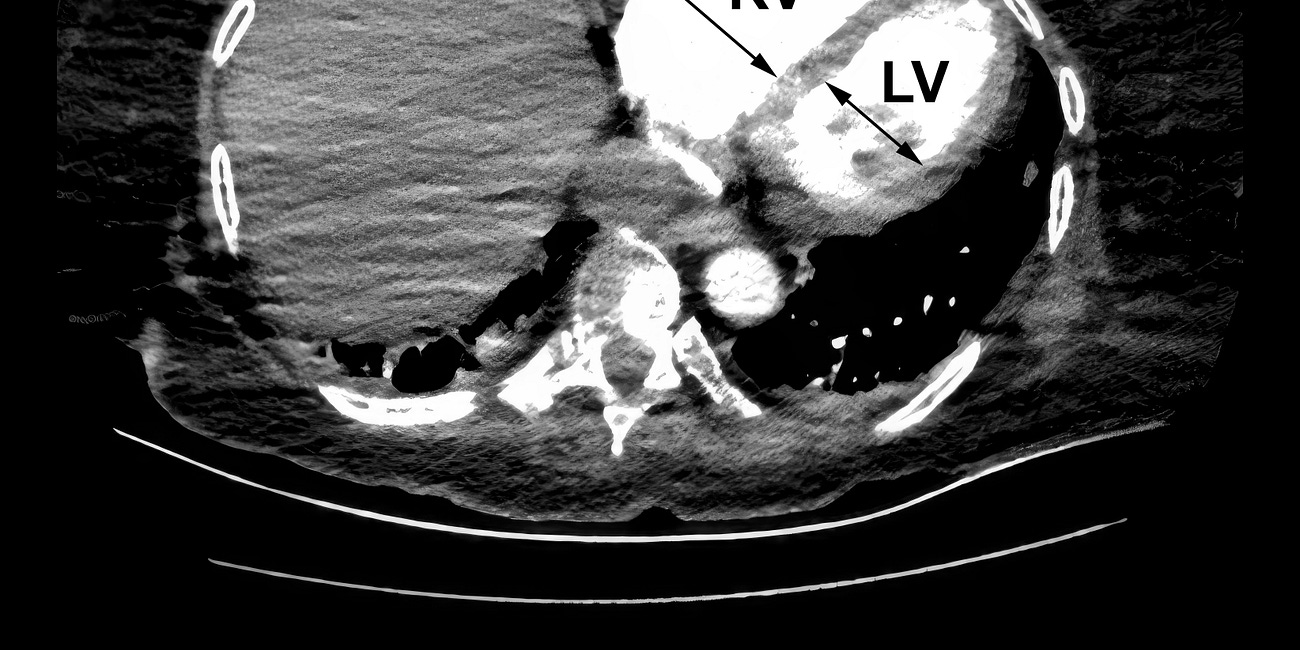

Transcatheter aortic-valve replacement (TAVR) and mitral transcatheter edge-to-edge repair (M-TEER) have emerged as lower-morbidity options for selected patients with severe aortic stenosis or mitral regurgitation. Transcatheter tricuspid valve replacement has proved to be more challenging.